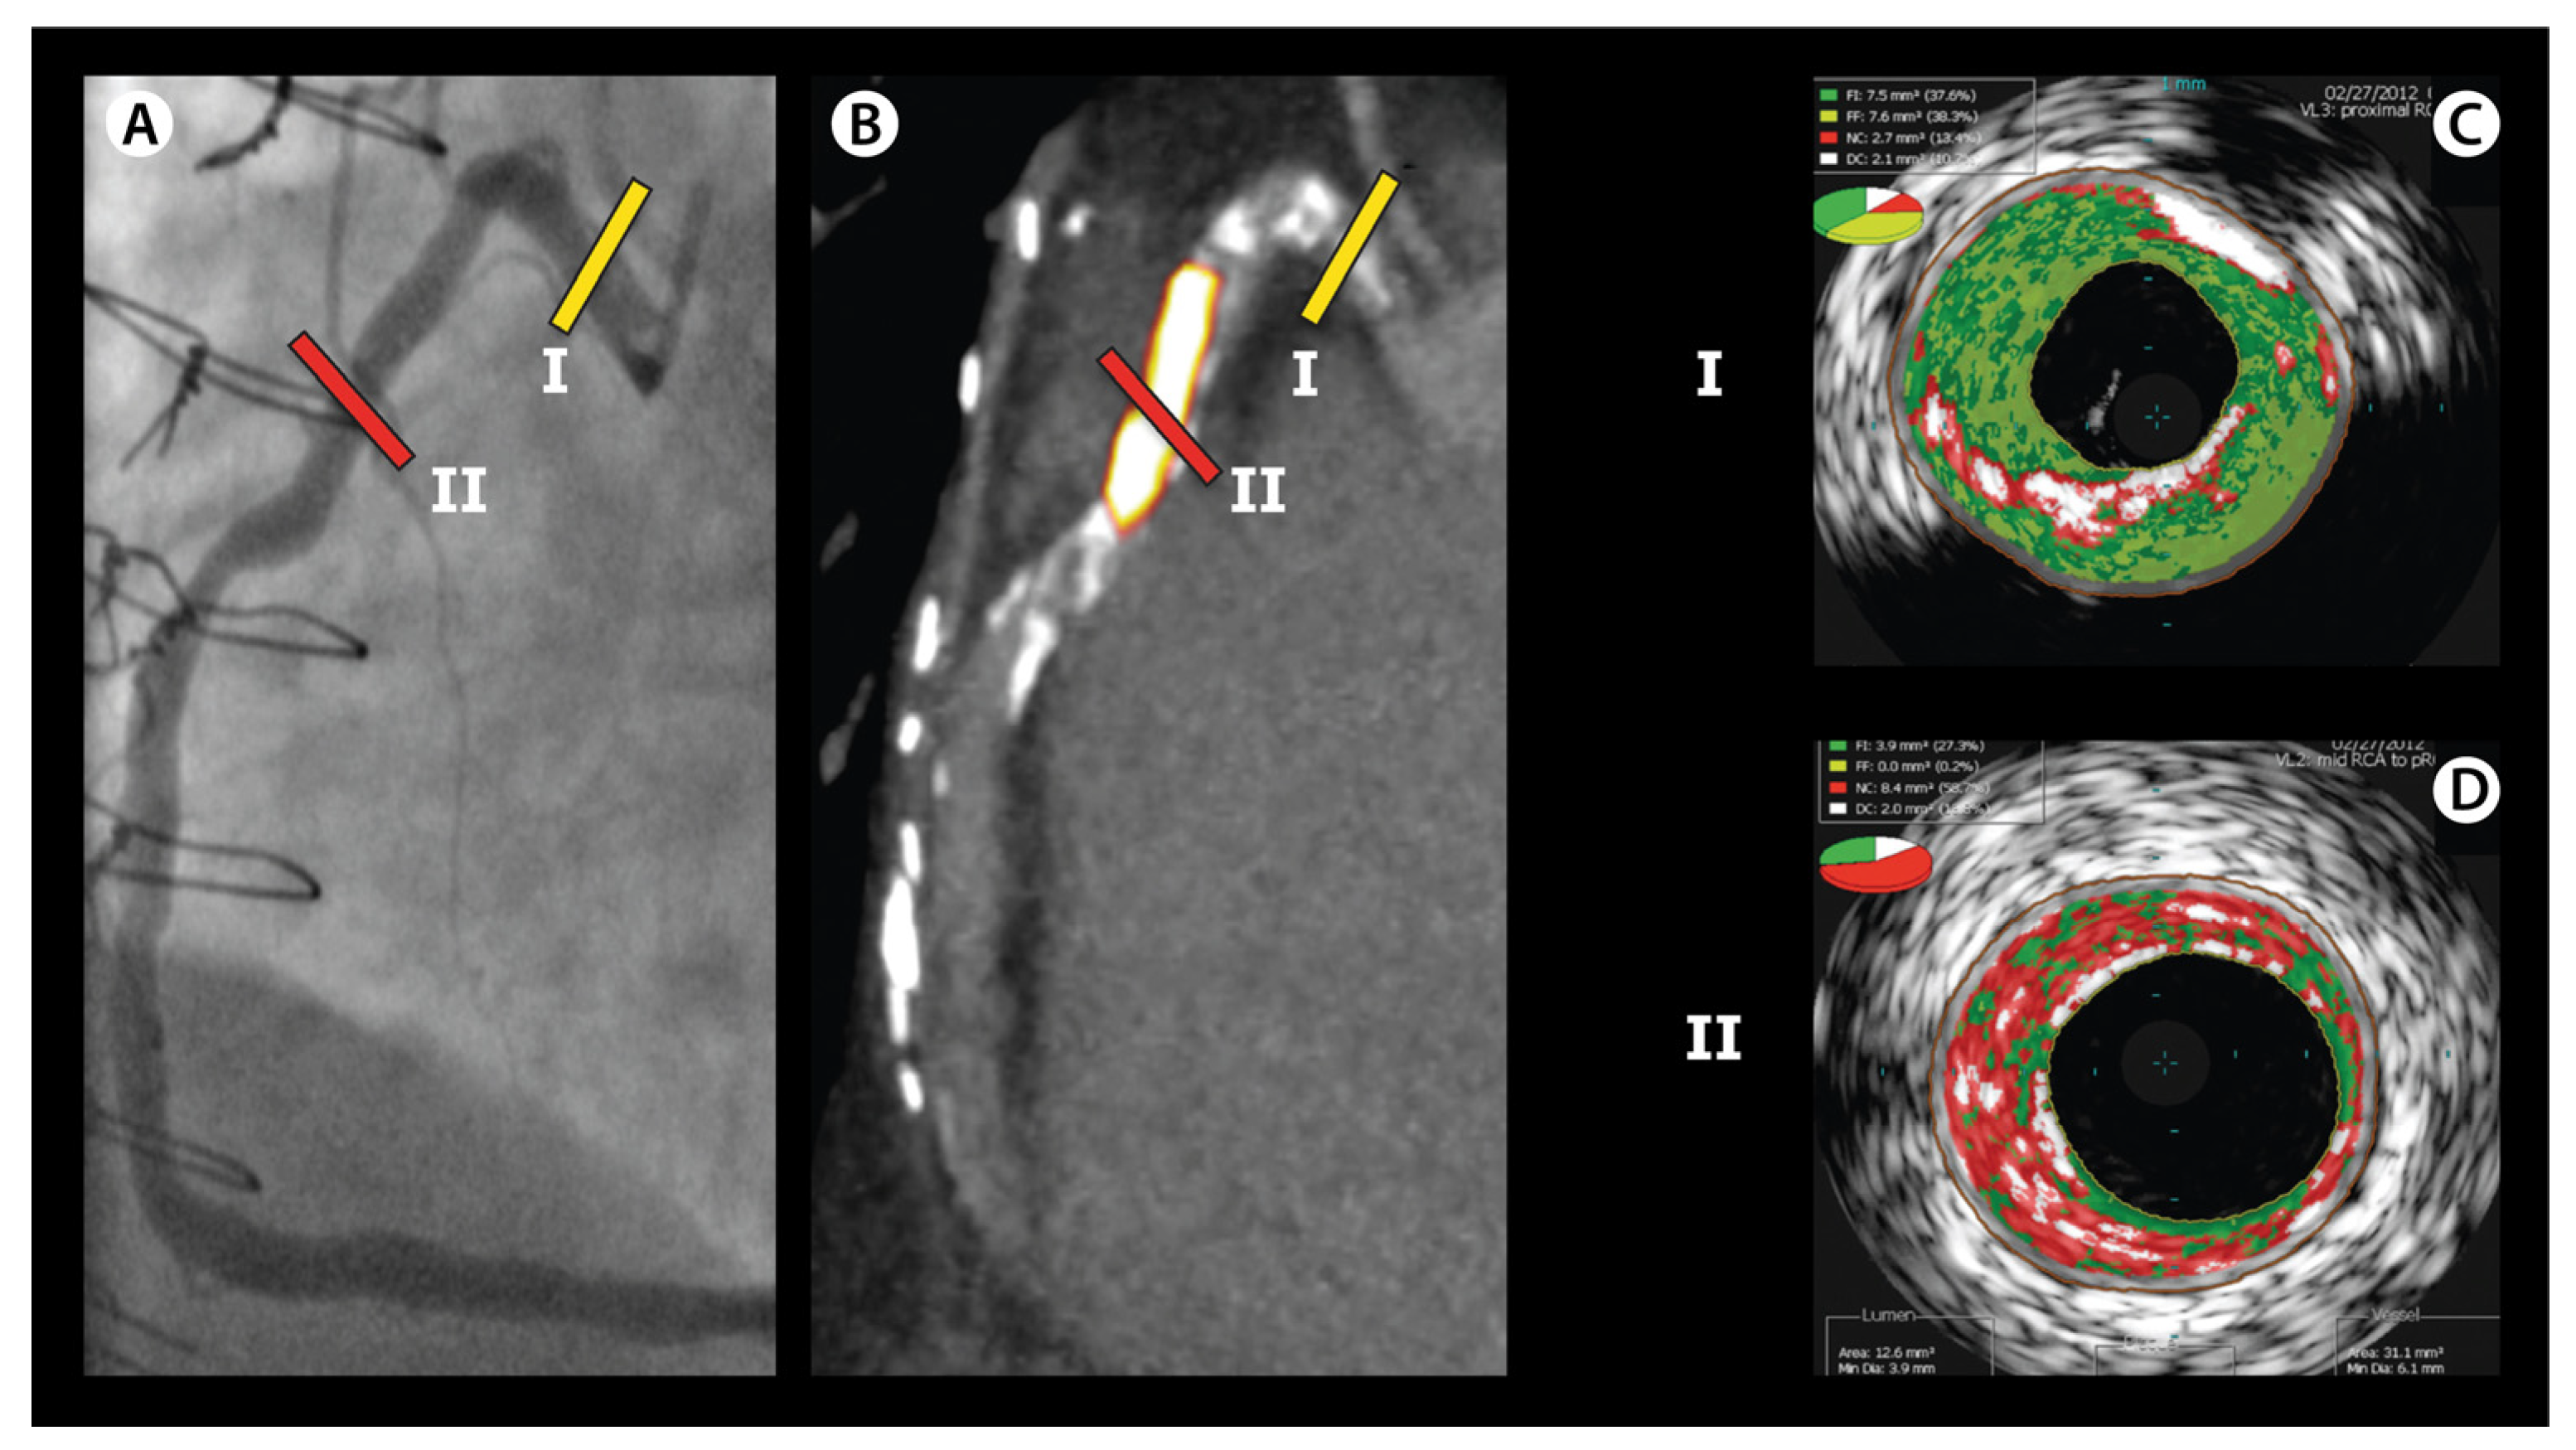

Jcm Free Full Text Detection Of Vulnerable Coronary Plaques Using Invasive And Non Invasive Imaging Modalities Html

Ecg Localization Of Myocardial Infarction Ischemia And Coronary Artery Occlusion Culprit Ecg Echo